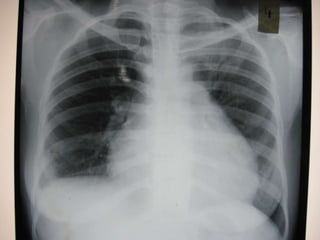

   After 2 weeks of antibiotic therapy

   Bouts of fever persisting

   Cough persisting

   Chest pain has become right sided

   Repeat chest X-Ray

   Suspicion shifted to the next accused:-

Lupus Pneumonitis